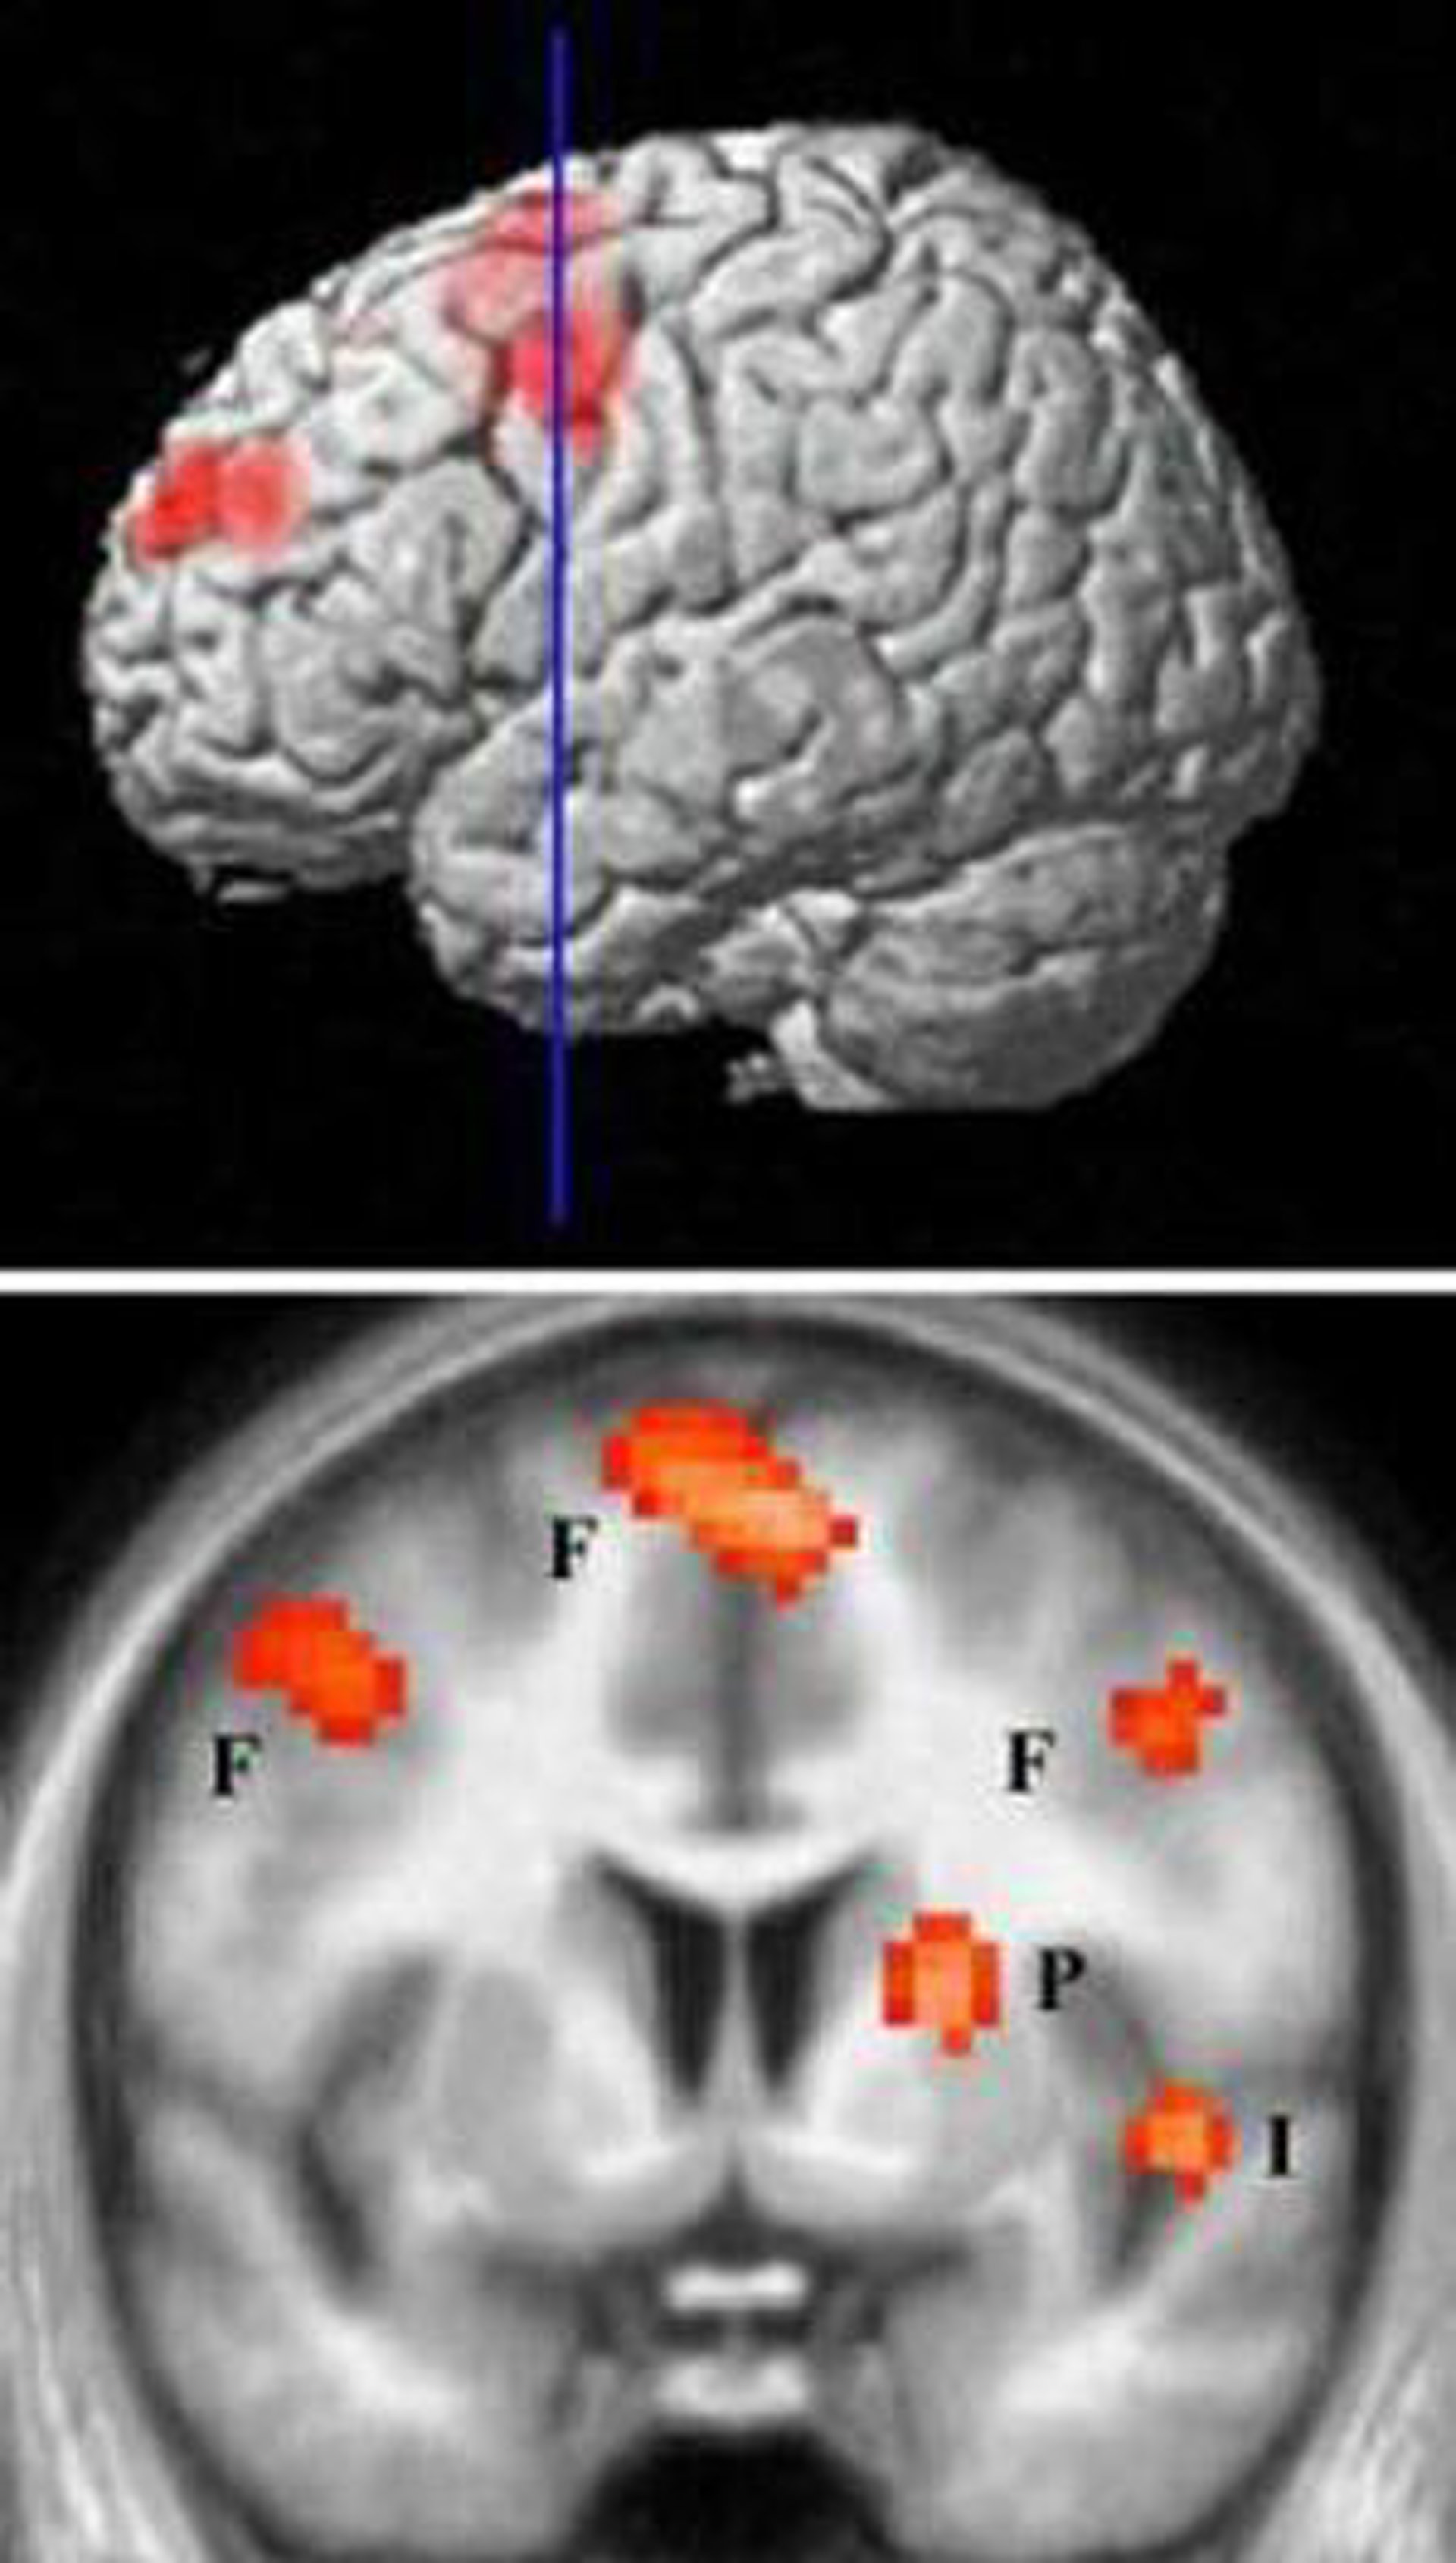

Para probar la idea de que la práctica de una nueva habilidad pueden en realidad producir cambios en la materia blanca, los científicos escanearon a un grupo de individuos antes y después de seis semanas de entrenamiento en malabares. Descubrieron cambios en el lóbulo parietal del cerebro, una región vinculada ya con las funciones visuales y del movimiento.

Además, los autores descubrieron cambios en la materia gris asociados al entrenamiento malabar que también estaban localizados en el mismo área que los cambios en la materia blanca. Según señalan los autores, esto sugiere que el entrenamiento influyó la estructura tanto de los cuerpos celulares de las neuronas como de sus proyecciones.